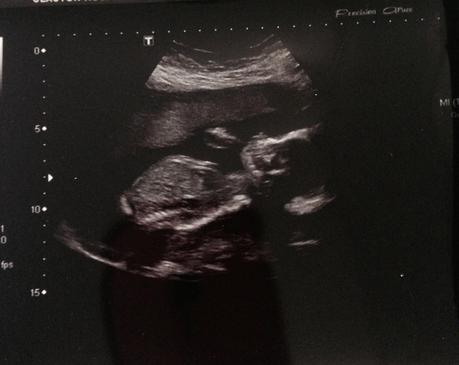

The huge positive in this week of feeling ill is that I had my 20 week scan Friday lunchtime and found out I am having a little girl!! I am so over the moon and emotional about it, I well up just thinking about meeting her. It really has made things very very real now.

The scan showed shes all fit, healthy and growing how she should be which is fantastic. She was also very nosey but when it came to trying to take the scan pic she wasn't having none of it. Camera shy like her daddy then, because we all know her mommy loves a selfie, haha!